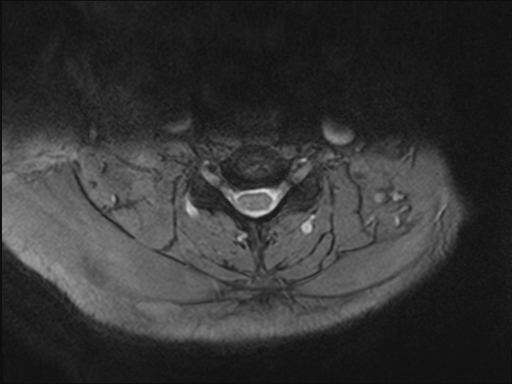

50 yr female was presented with neck and interscapular pain and was referred for MRI covering cervical spine and scapular region. On basis of findings on initial findings, patient was recalled for further MRI imaging.

What are the imaging findings and diagnosis?